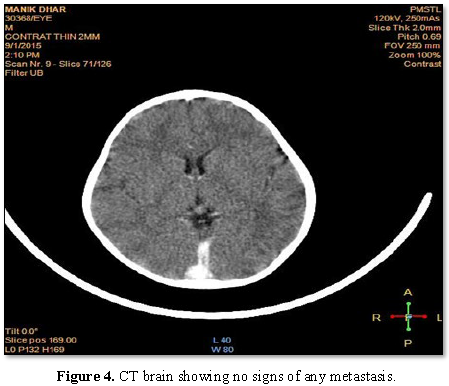

extraconal compartments of the left orbit. CT scan of the brain showed no signs

of intracranial extension. Lumber puncture, body scan and bone marrow biopsy

were performed to find out any metastasis. But there were no signs of